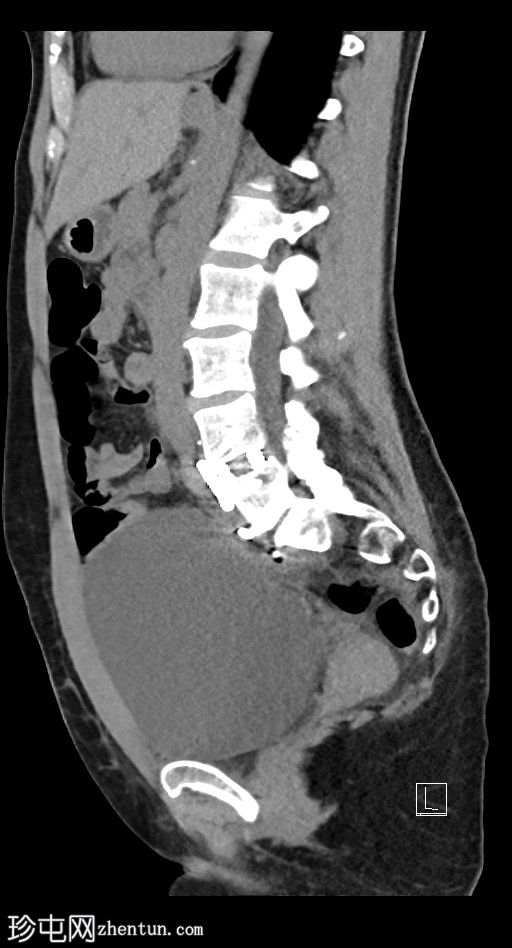

矢状位

平扫

左侧腹膜后可见一巨大囊性肿块,位于左侧腰大肌内侧,紧邻多个手术夹(ALIF手术所用),这些手术夹紧贴囊性肿块后壁。

膀胱已行引流管减压,并被囊性肿块向右侧推移。

子宫和左侧附件在囊性肿块前方保持正常的脂肪间隙,因此附件囊性病变的可能性较小。

左侧输尿管难以辨认,因为它位于囊性肿块下缘后方。